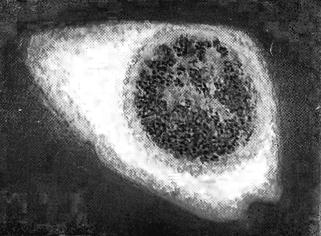

Рисунок 9 – Тельца Бабеша-Негри в нервных клетках головного мозга

На сегодняшний день в ветеринарии применяется единственный информативный и достаточно точный метод диагностики бешенства у животных. Это посмертное исследование срезов аммоновых рогов головного мозга и обнаружение в них специфических включений – телец Бабеша - Негри. Состоят тельца Бабеша - Негри из тонковолокнистого матрикса и вирусного рибонуклеопротеида.

3 Используя световой микроскоп, рассмотрите фиксированный препарат нейтроцитов с включениями рабдовирусов (тельца Бабеша-Негри). Сделайте рисунок препарата и укажите тельца Бабеша-Негри.